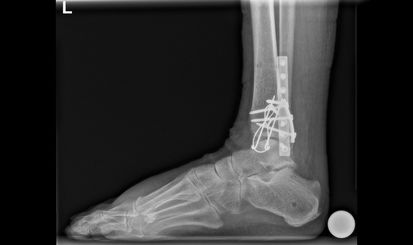

Beim Eingriff werden die Knochenbruchstücke von Altblut gesäubert und wieder in ihre anatomische Form gebracht. Die Fixation erfolgt dann mittels Schrauben und/oder Platten. Sollte die Knöchelgabel aufgrund einer Syndesmosenverletzung instabil sein, ist womöglich eine temporäre Stellschraubenfixation erforderlich. Diese Stellschraube wird 8 Wochen später ambulant wieder entfernt. Die anderen Schrauben werden nur entnommen, falls sie stören – meistens nach einem Jahr oder etwas früher.

Bild: Universitätsklinik Balgrist